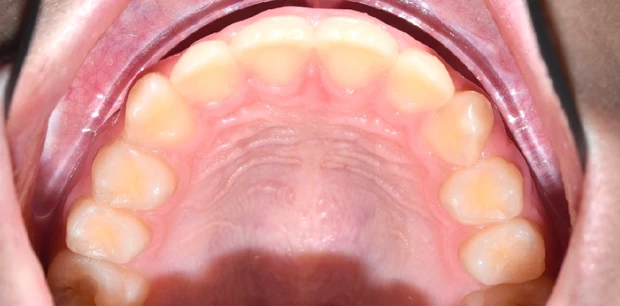

Профгигиена

Профессиональная гигиена зубов

Пациент Ф., 27 лет обратился с жалобами на периодическую кровоточивость десен при чистке зубов и на скученность зубов. Проведена профессиональная гигиена полости рта, пациент направлен на ортодонтическое лечение.